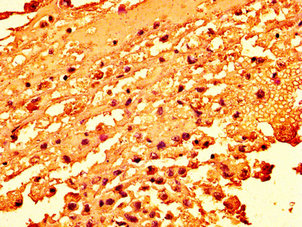

IHC image of CSB-PA010100OA04nme1HU diluted at 1:50 and staining in paraffin-embedded human melanoma performed on a Leica BondTM system. After dewaxing and hydration, antigen retrieval was mediated by high pressure in a citrate buffer (pH 6.0). Section was blocked with 10% normal goat serum 30min at RT. Then primary antibody (1% BSA) was incubated at 4°C overnight. The primary is detected by a biotinylated secondary antibody and visualized using an HRP conjugated SP system.